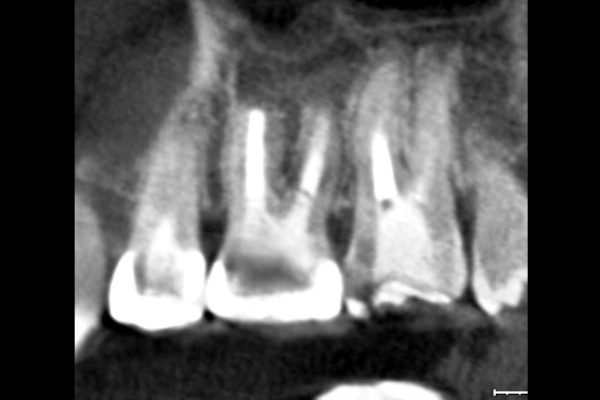

30代男性の前歯部の症例

- 治療回数2回、レントゲン写真で治癒を確認できるまでの期間6ヶ月

4.根管の封鎖(逆根管充填)

- 少しでも汚染物質が残ると再発のリスクが高まります。